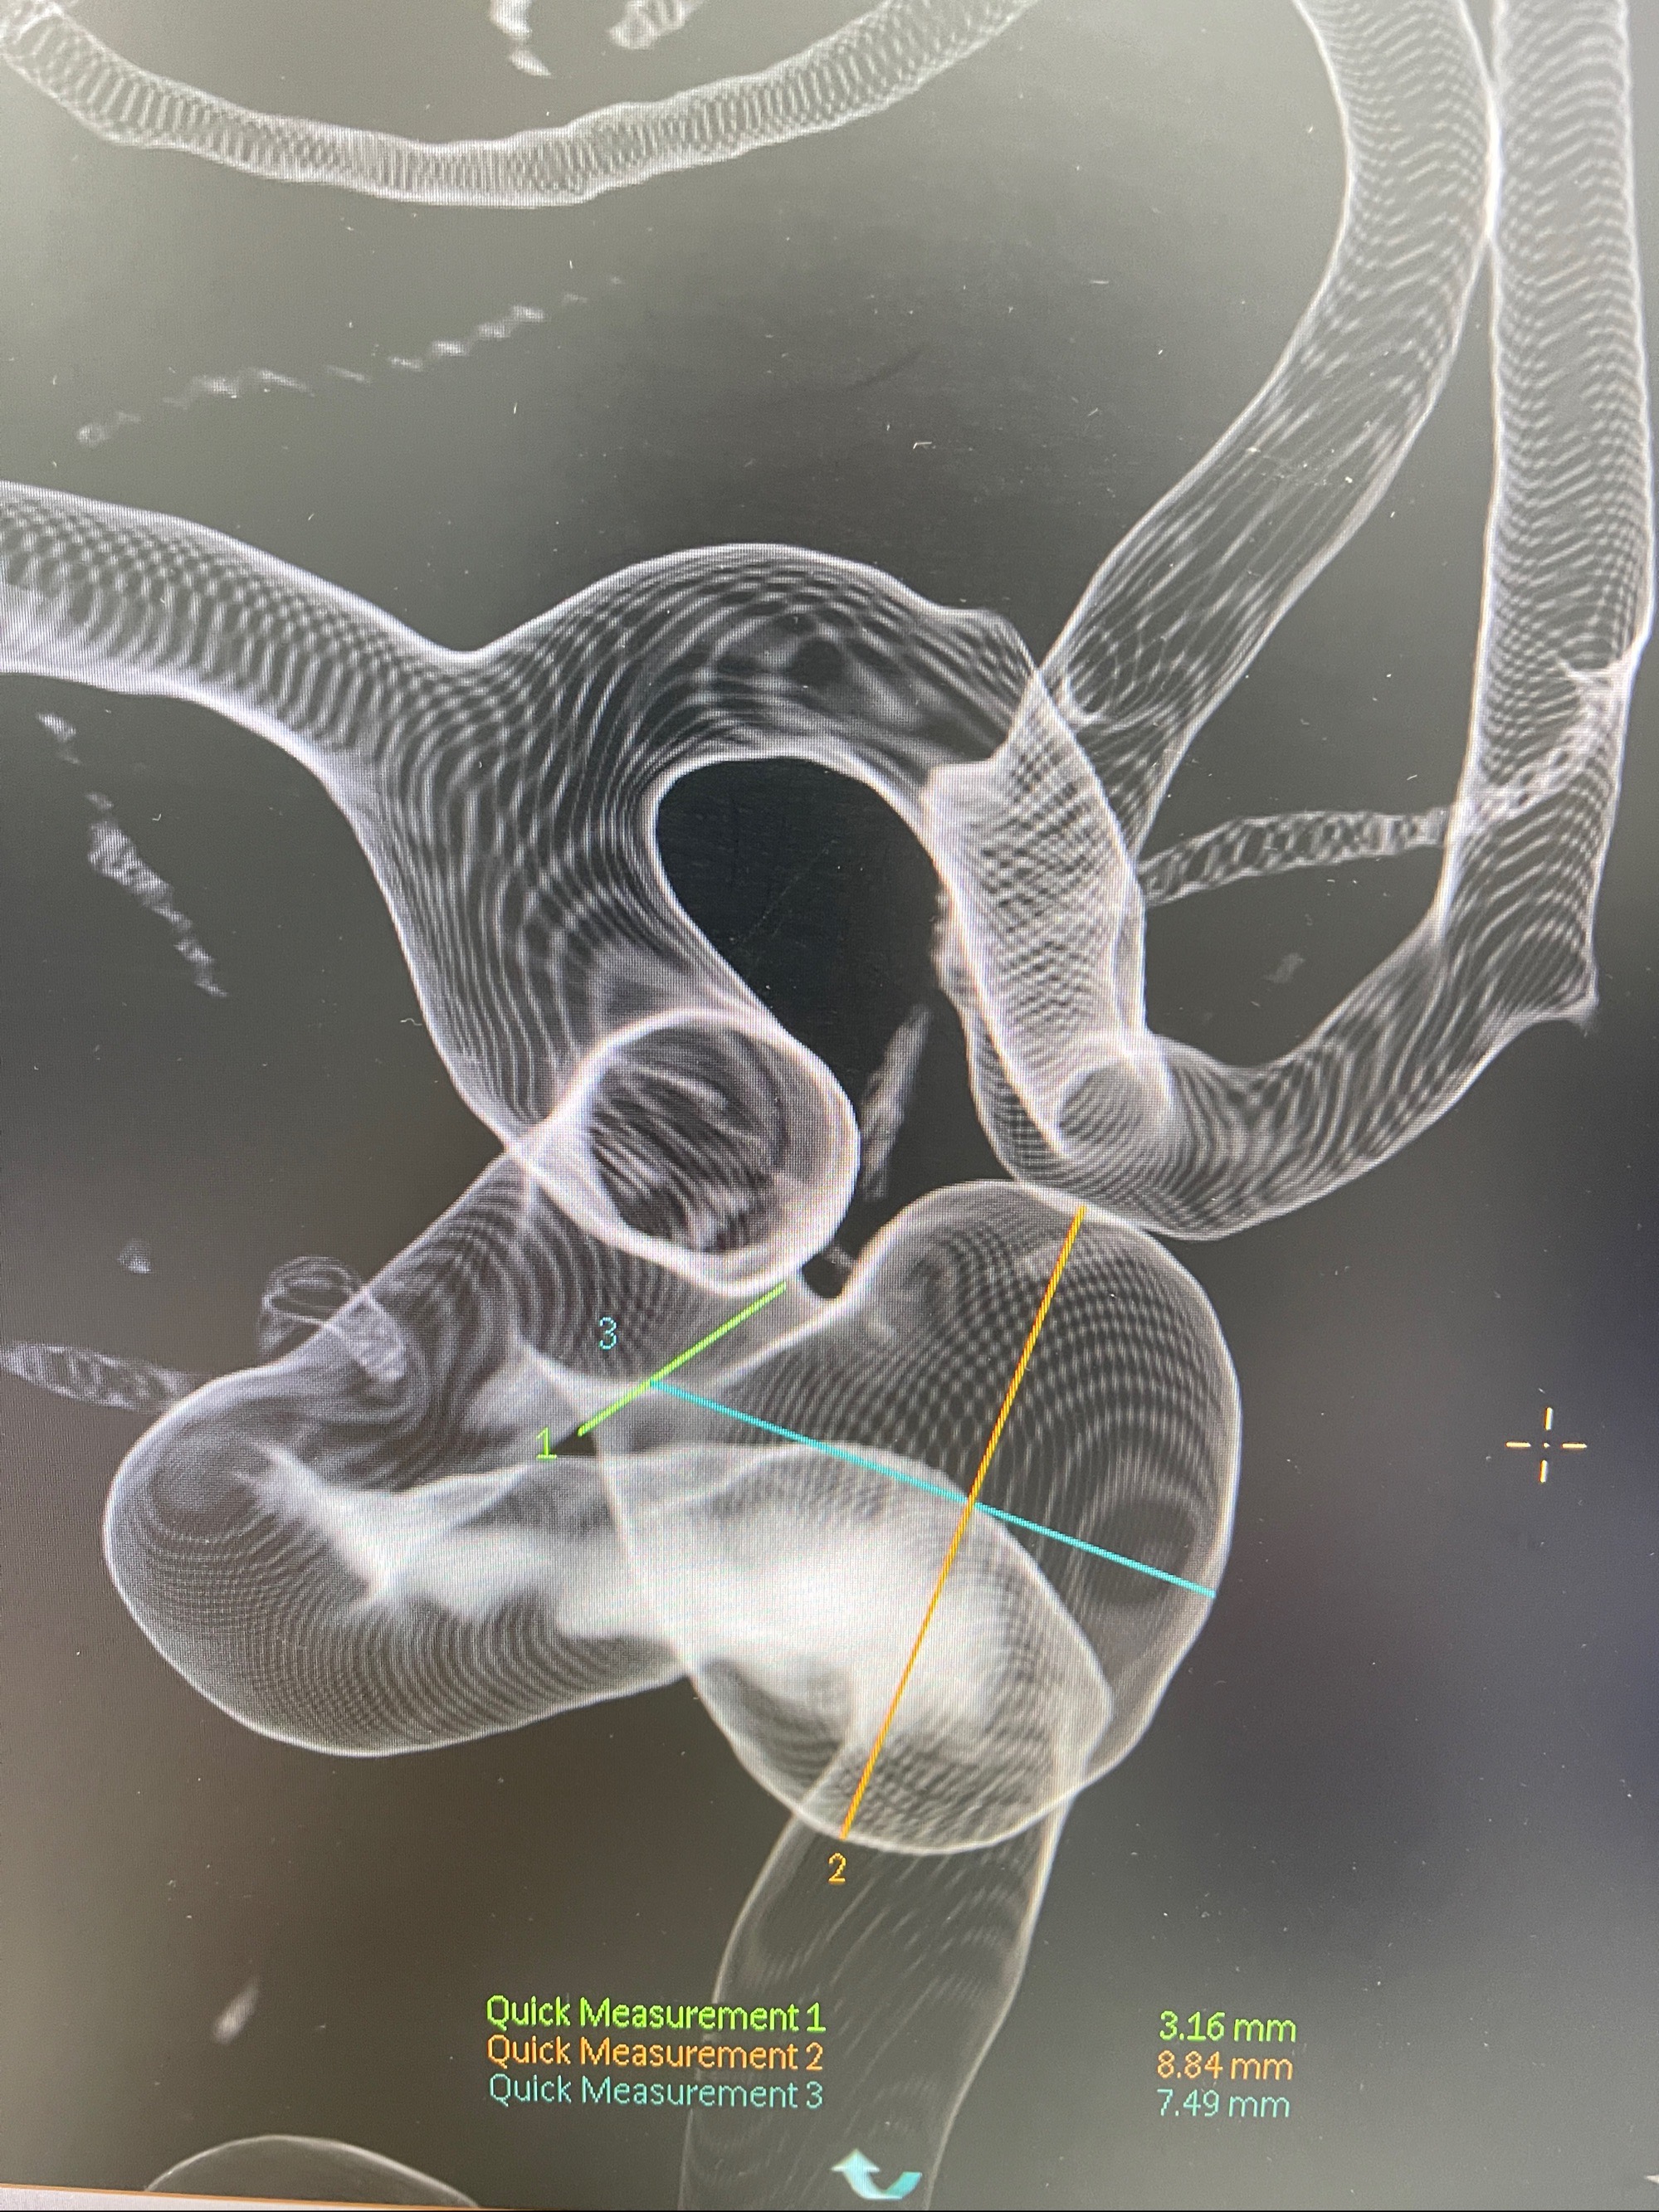

2023-08-30DSA:左侧颈内动脉眼动脉动脉瘤,约3*9.2*7.3mm大小

术后3D显示支架贴壁佳